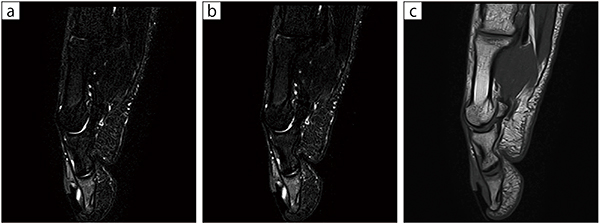

■症例1:母趾骨髄炎

19歳,男性。2mmの薄いスライス厚かつ短時間撮影でも,REALIZE Plusで十分なSNRを担保できた(a)。

a:STIR,SAG,スライス厚:2mm,scantime1:17,TR/TE:4000/80,REALISE Plusあり

b:STIR,SAG,スライス厚:2mm,scantime2:13,TR/TE:4000/80,REALISE Plusなし

c:T1WI,SAG,スライス厚:2mm,scantime1:26,TR/TE:506/14.8